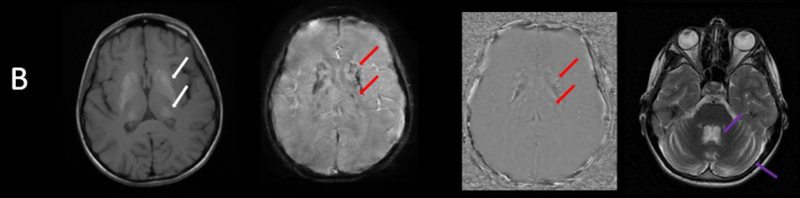

- A) Aksiyel FLAIR görüntülerde parietooksipital lobda kortikal hiperintensite (ok) ve difüzyon görüntülerde kısıtlanma alanları izleniyor (oklar). Ertesi gün çekilen kontrol MRG’de FLAIR serilerde yeni gelişen oksipital bölgede kortikal hiperintensite (ok) izlenmektedir.

- B) Aksiyel T1A görüntülerde her iki lentiform ve kaudat nukleuslarda, talamuslarda simetrik hiperintensite (oklar) izleniyor. Bu düzeyde tariflenen sinyallerin SWI ve faz görüntülerde kalsifikasyon ile uyumlu olduğu görülmektedir (oklar). T2A görüntüde yaş ile uyumsuz serebellar atrofi ile uyumlu foliada derinleşme ve 4. ventrikül genişliğinde artış izlenmektedir (oklar).